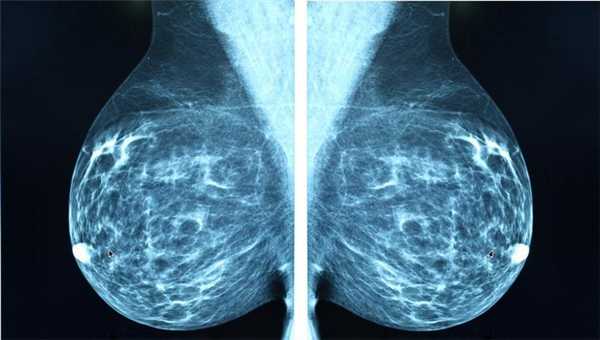

Классический рентген по-прежнему остаётся важным методом для диагностики самых разных заболеваний. Например, маммография (рентгеновское исследование молочных желез) - лучший способ скрининга рака молочной железы. Возможности КТ в выявлении злокачественных и воспалительных процессов в этом органе существенно ниже.

Маммография

Отдельный вид рентгенографии, разработанный для диагностики заболеваний молочной железы, поэтому проходят маммографию женщины. О рекомендуемом возрасте для проведения процедуры единого мнения нет. Маммография помогает убедиться в отсутствии злокачественной опухоли с точностью до 89%. Считается, что женщины должны проходить обследования регулярно, начиная с 39 лет, хотя некоторые онкологические сообщества рекомендуют обследоваться с более молодого возраста.

Маммографию назначают для диагностики рака молочной железы, процедура проходит быстро, это плюс, но пациентку облучают, а риск неверного диагноза остаётся, это минус. Маммография может быть цифровой и плёночной, цифровая маммография обеспечивает получение более чёткого снимка.